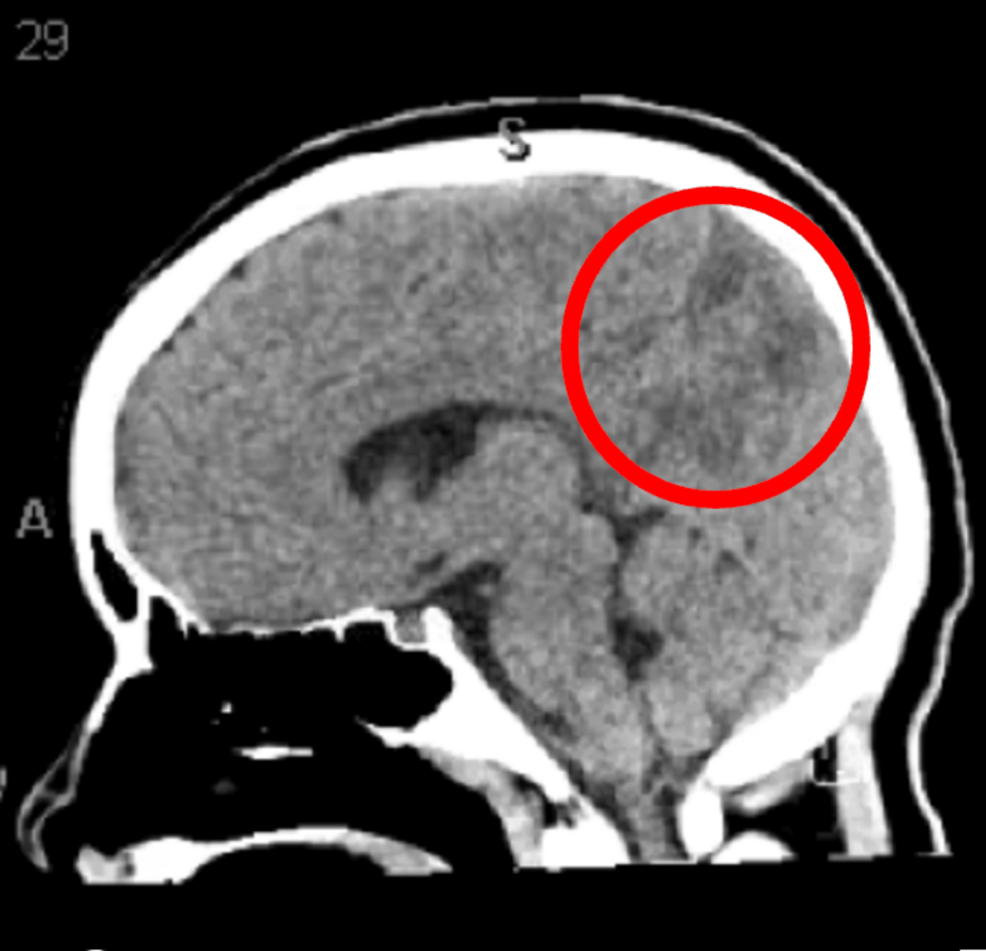

PREPS is a neurological condition characterized by headache, altered mental status, seizures, and visual disturbances. It’s often, though not always, reversible with prompt treatment. Eclampsia, a severe complication of pregnancy marked by seizures in a woman with pre-eclampsia, is a significant risk factor. The case report highlights the challenges of diagnosing PREPS in adolescents, where symptoms can be atypical and quickly attributed to other postpartum issues. The underlying mechanism isn’t fully understood, but it’s believed to involve cerebral vasoconstriction and edema, often triggered by abrupt changes in blood pressure. **Posterior Reversible Encephalopathy Syndrome** is increasingly recognized as a spectrum disorder, with varying degrees of severity and reversibility.

Currently, PREPS diagnosis relies heavily on neuroimaging (MRI) to visualize the characteristic edema. However, research is underway to identify specific biomarkers that could facilitate earlier and more accurate diagnosis. These biomarkers could include proteins associated with endothelial dysfunction, inflammation, or blood-brain barrier disruption. The development of a reliable biomarker would revolutionize PREPS management, allowing for proactive intervention before irreversible neurological damage occurs.